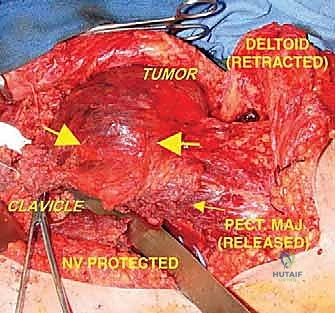

2. الشق الجراحي والوصول الآمن (Incision & Exposure)

يتم عمل شق جراحي واسع يسمح بالوصول الكامل للكتف. الخطوة الأهم هنا هي استئصال مسار إبرة الخزعة السابقة بالكامل مع الجلد المحيط بها لمنع أي زرع لخلايا سرطانية في الجرح الجديد.

3. التسليك الوعائي والعصبي (Neurovascular Dissection)

هذه هي المرحلة الأكثر خطورة. باستخدام أدوات الجراحة الميكروسكوبية وعدسات التكبير، يقوم الدكتور هطيف بفصل الشريان والوريد الإبطي، والضفيرة العضدية عن كتلة الورم. يتطلب هذا دقة متناهية، فأي خطأ قد يؤدي إلى نزيف حاد أو شلل دائم في اليد.

4. استئصال الورم ككتلة واحدة (En-bloc Resection)

يتم قطع العظام (العضد، الترقوة، أو لوح الكتف حسب امتداد الورم) باستخدام مناشير جراحية دقيقة. يتم استخراج الورم مغلفاً بطبقة من الأنسجة السليمة (هوامش الأمان). يتم إرسال عينات من الحواف فوراً إلى مختبر الباثولوجي أثناء العملية (Frozen Section) للتأكد من خلوها تماماً من الخلايا السرطانية.

6. التغطية بالأنسجة الرخوة وإغلاق الجرح (Soft Tissue Coverage)

بسبب إزالة كمية كبيرة من العضلات والجلد مع الورم، قد يتطلب الأمر نقل سدائل عضلية (Muscle Flaps)، مثل العضلة الظهرية العريضة (Latissimus Dorsi Flap)، لتغطية المفصل الصناعي وحماية الأوعية الدموية، ثم إغلاق الجرح تجميلياً.